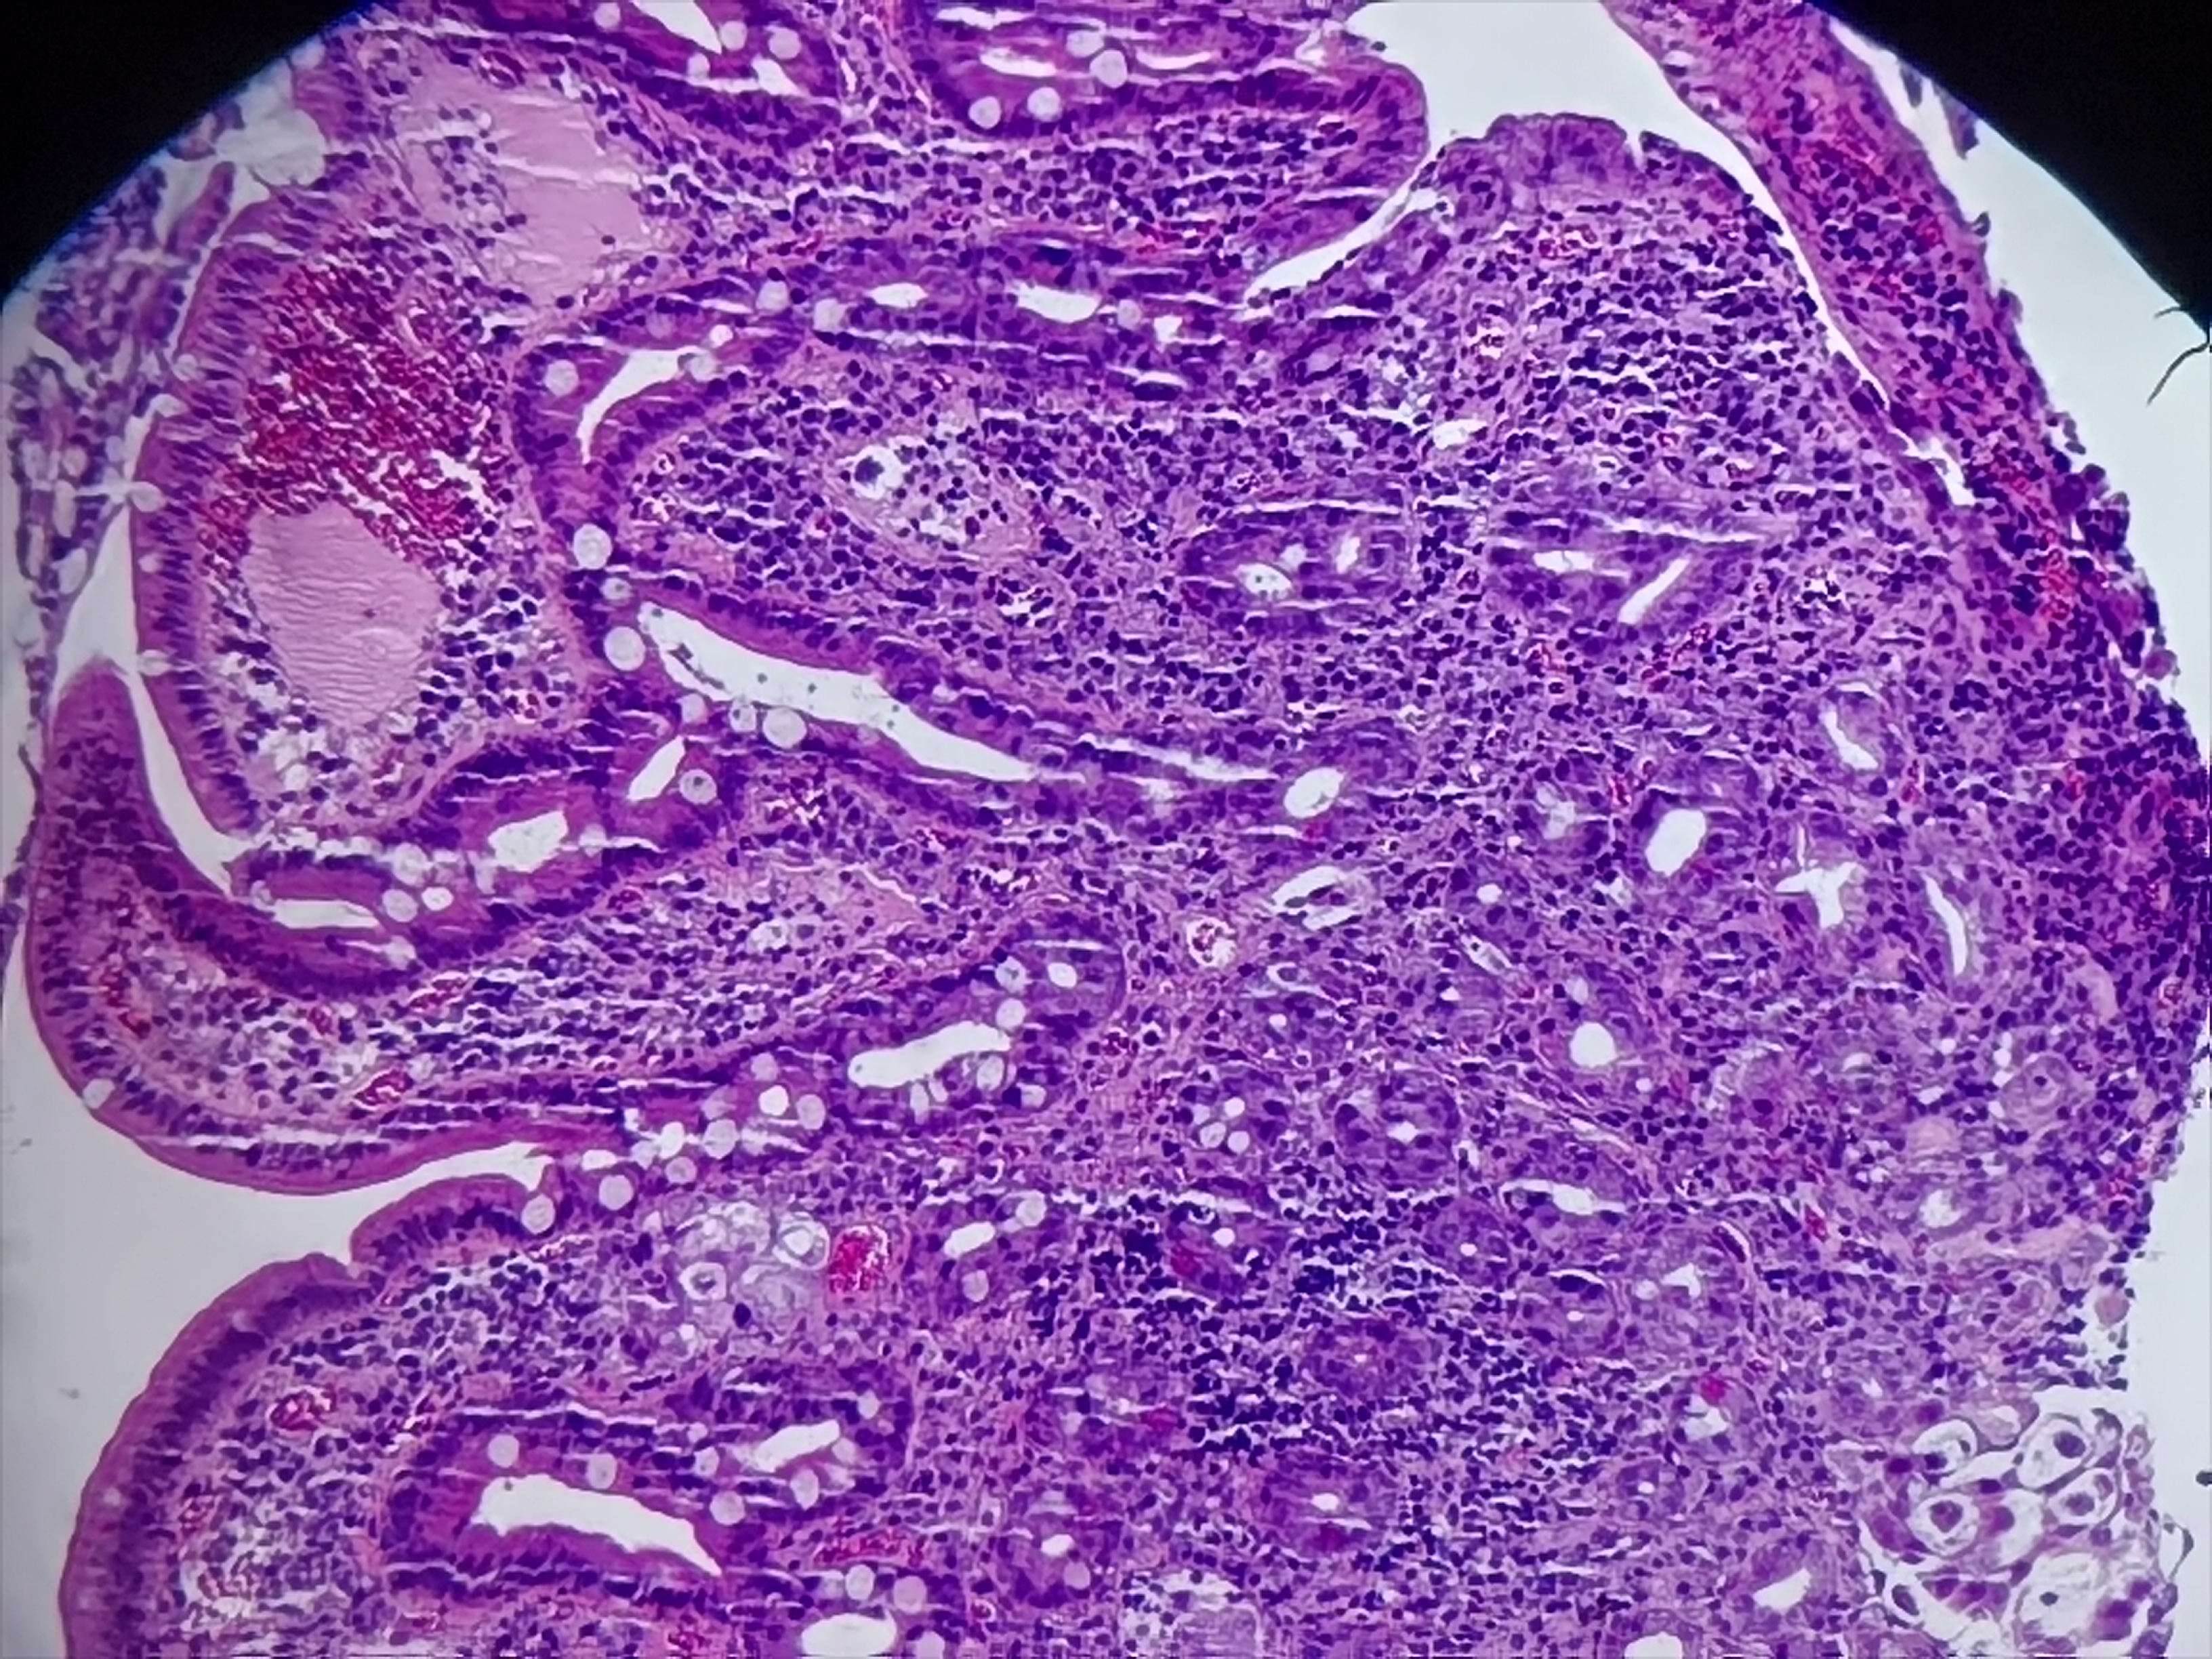

十二指肠球部活检

性别

女

年龄

66岁

临床诊断

一般病史

十二指肠球部可见一大小约0.5*0.6cm隆起性病变

标本名称

十二指肠球部粘膜活检

大体所见

灰白灰红组织1块

急,请教老师。

图1

异位胰腺组织。